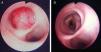

O estudo analítico mostrou uma ligeira elevação da proteína C reactiva (4,7mg/dl). A radiografia torácica sugeriu a presença de uma pneumonia obstrutiva, que foi confirmada pelos achados da tomografia computadorizada (TC) demonstrando uma massa no BPD e uma consolidação com broncograma aéreo no lobo médio com um pequeno derrame pleural homolateral loculado (fig. 1A e B). A broncofibroscopia revelou um tumor polipóide de superfície lisa e vascularizada no BPD, junto à carina principal, com uma base de inserção limitada, emergindo da parede brônquica medial, condicionando obstrução de mais de 90% do seu lúmen (fig. 2A e B).

A excisão da lesão foi efectuada utilizando a fotocoagulação com neodínio: yttrium-aluminum-garnet (Nd:YAG) laser com auxílio da remoção mecânica através da broncoscopia rígida (BR), obtendo-se repermeabilização total do BPD numa sessão (fig. 2B). Não foram documentadas complicações decorrentes do procedimento.